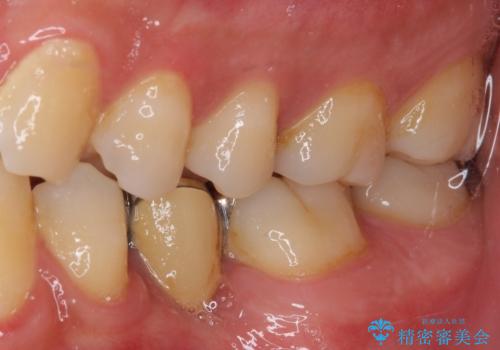

- 奥歯の銀歯が頻繁に外れるとのことで来院された患者様です。

欠損部分をインレーによるブリッジで治療してありましたが、外れやすく虫歯リスクが高いため、オールセラミックブリッジにて補綴することとしました。